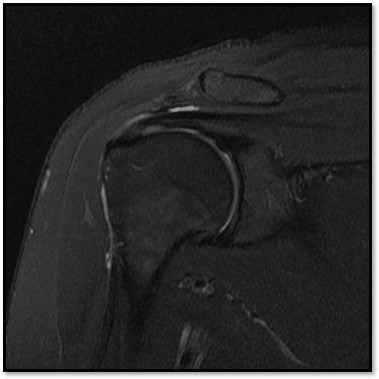

MRI와 초음파를 다시 검토했습니다.

회전근개 극상건의 관절면측(articular-side) 부분파열.

관절면측(articular-side) 파열은 회전근개의 아래쪽, 즉 관절에 면한 부분이 손상된 것입니다.

MRI: 극상건 관절면측 부분파열 (약 40%)

MRI: 극상건 관절면측 부분파열 (약 55%)

MRI: 극상건 관절면측 부분파열 (약 30%)